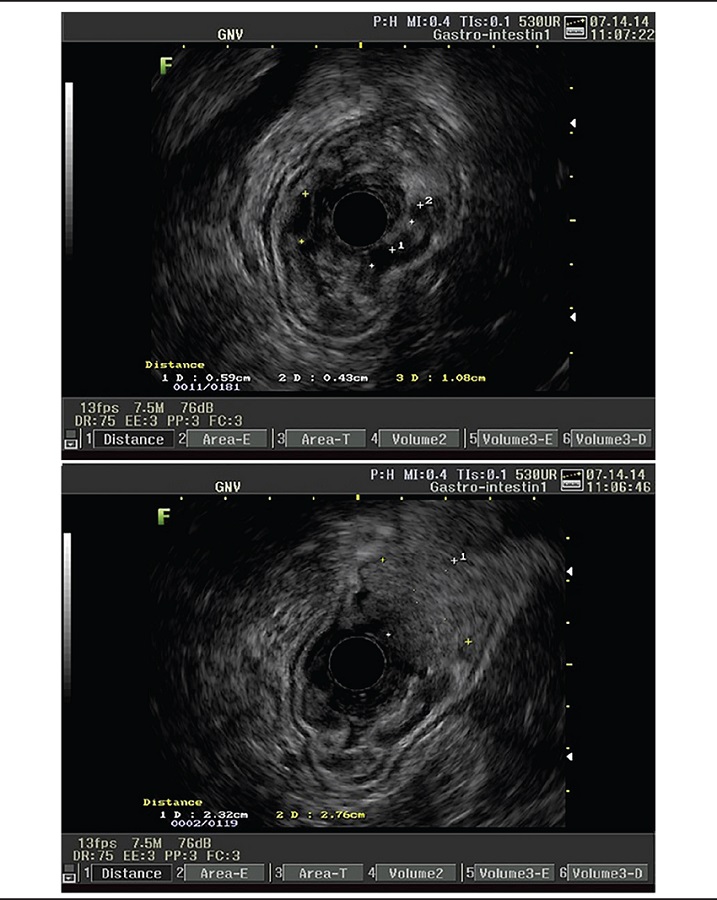

Subsequent echoendoscopy had been performed as a complementary propaedeutic procedure in order to rule out other possible differential diagnoses or associated diseases, considering the patient's evolution of eight years, uncommon in MD cases (Figure 4).

Echoendoscopy showed a marked thickening of the entire gastric wall, which measured 12 mm, mainly the mucous layer (8 mm), which is hypoechoic, with the presence of several cysts measuring 5 to 10 mm (normal wall thickness is up to 5 mm). The stratification of the gastric wall was preserved, with the submucosa and muscular layers identified. The gastric wall thickening was diffuse, from the cardia to the pylorus. The polypoid lesion measured, in its largest extensions, 5 × 3 cm with heterogeneous appearance. It is worth noting that it is another interesting aspect of the case, since cystic formations, such as those observed, are not typical of Ménétriér hypertrophic gastropathy.

The propaedeutic feature of the echoendoscopy assumes an important role in the case because of its atypical and long-lasting presentation (about 8 years), and is indicated as a complementary propaedeutic(11), with findings as MD when revealing a localized, hyperechoic mucosal layer thickening and/or one or more gastric folds of thickness greater than 10 mm, however the UGE and the anatomopathological study are the gold standard for the diagnosis of the disease.